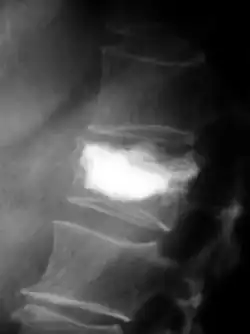

Magnetresonanztomografie

Mit der Magnetresonanztomografie (MRT) können insbesondere Weichteilgewebe gut bildmäßig dargestellt werden. Sie gilt für die Diagnostik von spinalen Metastasen (Metastasen in der Wirbelsäule) als Goldstandard. Mit der MRT können darüber hinaus weitere Komplikationen im Bereich der spinalen Metastasen, wie beispielsweise Infektionen oder Verletzungen des Bandscheiben- und Ligamentkomplexes, Knochenmarködeme nach einer frischen Fraktur,[117][118] oder Kompressionen neuraler Strukturen, sichtbar gemacht werden.[18]:16 Mit Hilfe der STIR-Sequenz (engl. short tau inversion recovery) ist es möglich, das Alter einer Fraktur zu ermitteln. Zum Aufspüren von Metastasen ist die T1-Wichtung mit Gadolinium-haltigen Kontrastmitteln, wie beispielsweise Gadotersäure, besonders gut geeignet. Das Kontrastmittel reichert sich in den Metastasen besonders stark an.[18][119]